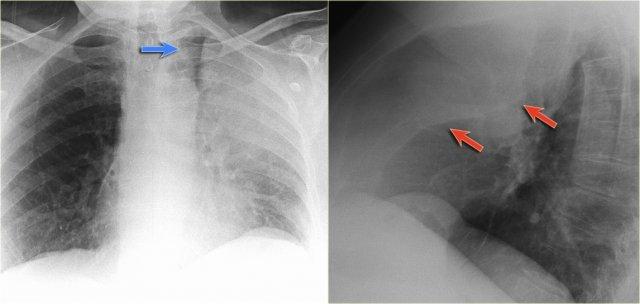

Xẹp thùy trên phổi phải

Hãy quan sát kỹ các hình ảnh trước, sau đó tiếp tục đọc.

Các dấu hiệu:

- Đám mờ hình tam giác

- Rốn phổi phải nâng cao

- Xóa mờ khoang sáng sau xương ức (mũi tên)

Trên PET-CT ghi nhận một khối u phổi kèm theo xẹp thùy trên phổi phải do tắc nghẽn phế quản thùy trên.

Một dấu hiệu thường gặp trong xẹp thùy trên phổi phải là hiện tượng ‘lều hóa’ cơ hoành (mũi tên xanh dương).

Bệnh nhân này có ung thư phổi vị trí trung tâm kèm di căn ở cả hai phổi (mũi tên đỏ).